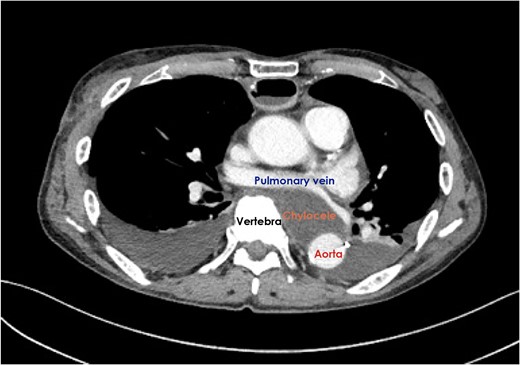

Enteral feeding with low-fat elemental formula was commenced in the morning on postoperative Day (POD) 1; however, hemodynamic instability suddenly developed in the afternoon on the same day. Echocardiography performed during cardiopulmonary resuscitation demonstrated massive pericardial effusion. Emergency ultrasound-guided drainage was performed via the subxyphoid approach; 350 mL of serous fluid was drained, and the patient’s hemodynamic status dramatically improved. After changing to fat-containing polymeric formula on POD 5, a small amount of chylous fluid was contained in the pericardial drainage fluid, but not in the bilateral pleural drainage fluid. Because the chylous fluid disappeared immediately after returning to the elemental formula, the right pleural, pericardial, and left pleural drains were removed sequentially. A fat-reduced diet was given to the patient; however, the cardiac tamponade relapsed and the pericardial drain was re-inserted on POD 13. A computed tomography scan demonstrated the presence of a retrocardiac fluid collection, encompassed by the left pulmonary vein and left atrium, descending aorta and vertebral column (Fig. 1). The initial pericardial drainage fluid was serous, but it changed to chylous again after a challenge with polymeric formula. Under the diagnosis of chylopericardial tamponade communicating with a posterior mediastinal chylocele, surgical exploration was performed via the left-sided thoracoscopic approach on POD 20. A chyle leak from a tributary of the thoracic duct was easily recognized because of the administration of polymeric formula immediately before surgery. The leak was stopped with surgical clips. A pericardial hole, which had been made during the esophagectomy, was confirmed to be close to the leakage point (Fig. 2). The hole was left open and a closed suction drain was placed in the posterior mediastinum.

Computed tomography scan demonstrated the presence of a retrocardiac fluid collection when the cardiac tamponade relapsed.

The anatomical characteristics of this patient should be considered when discussing the development of this exceptionally rare complication. As shown in Fig. 1, the descending aorta was located dorsally in the left thoracic cavity; therefore, a space was encompassed by the left pulmonary vein and atrium, descending aorta and vertebral column. A bulky esophageal tumor occupied this space before the operation, while a chylocele replaced the tumor after it was removed. As reported by Rottoli et al. [2], chylous fluid would usually drain into the right thoracic cavity, even if a chylocele developed in the posterior mediastinum. Interestingly, vertebral column prevented chylous fluid from draining into the right thoracic cavity in this patient; therefore, no chyle drainage from the right chest tube was seen throughout the clinical course. Moreover, no chylous fluid drained into the left thoracic cavity either, although the left mediastinal pleura was partially resected with tumor of the mid-thoracic esophagus at the initial operation. The second operation revealed that the opened pleura was already covered by the left lung, which tightly adhered to the descending aorta. Because of this completely isolated space, increased chylous fluid would flow into the hypobaric pericardial space through a small hole in the pericardium.